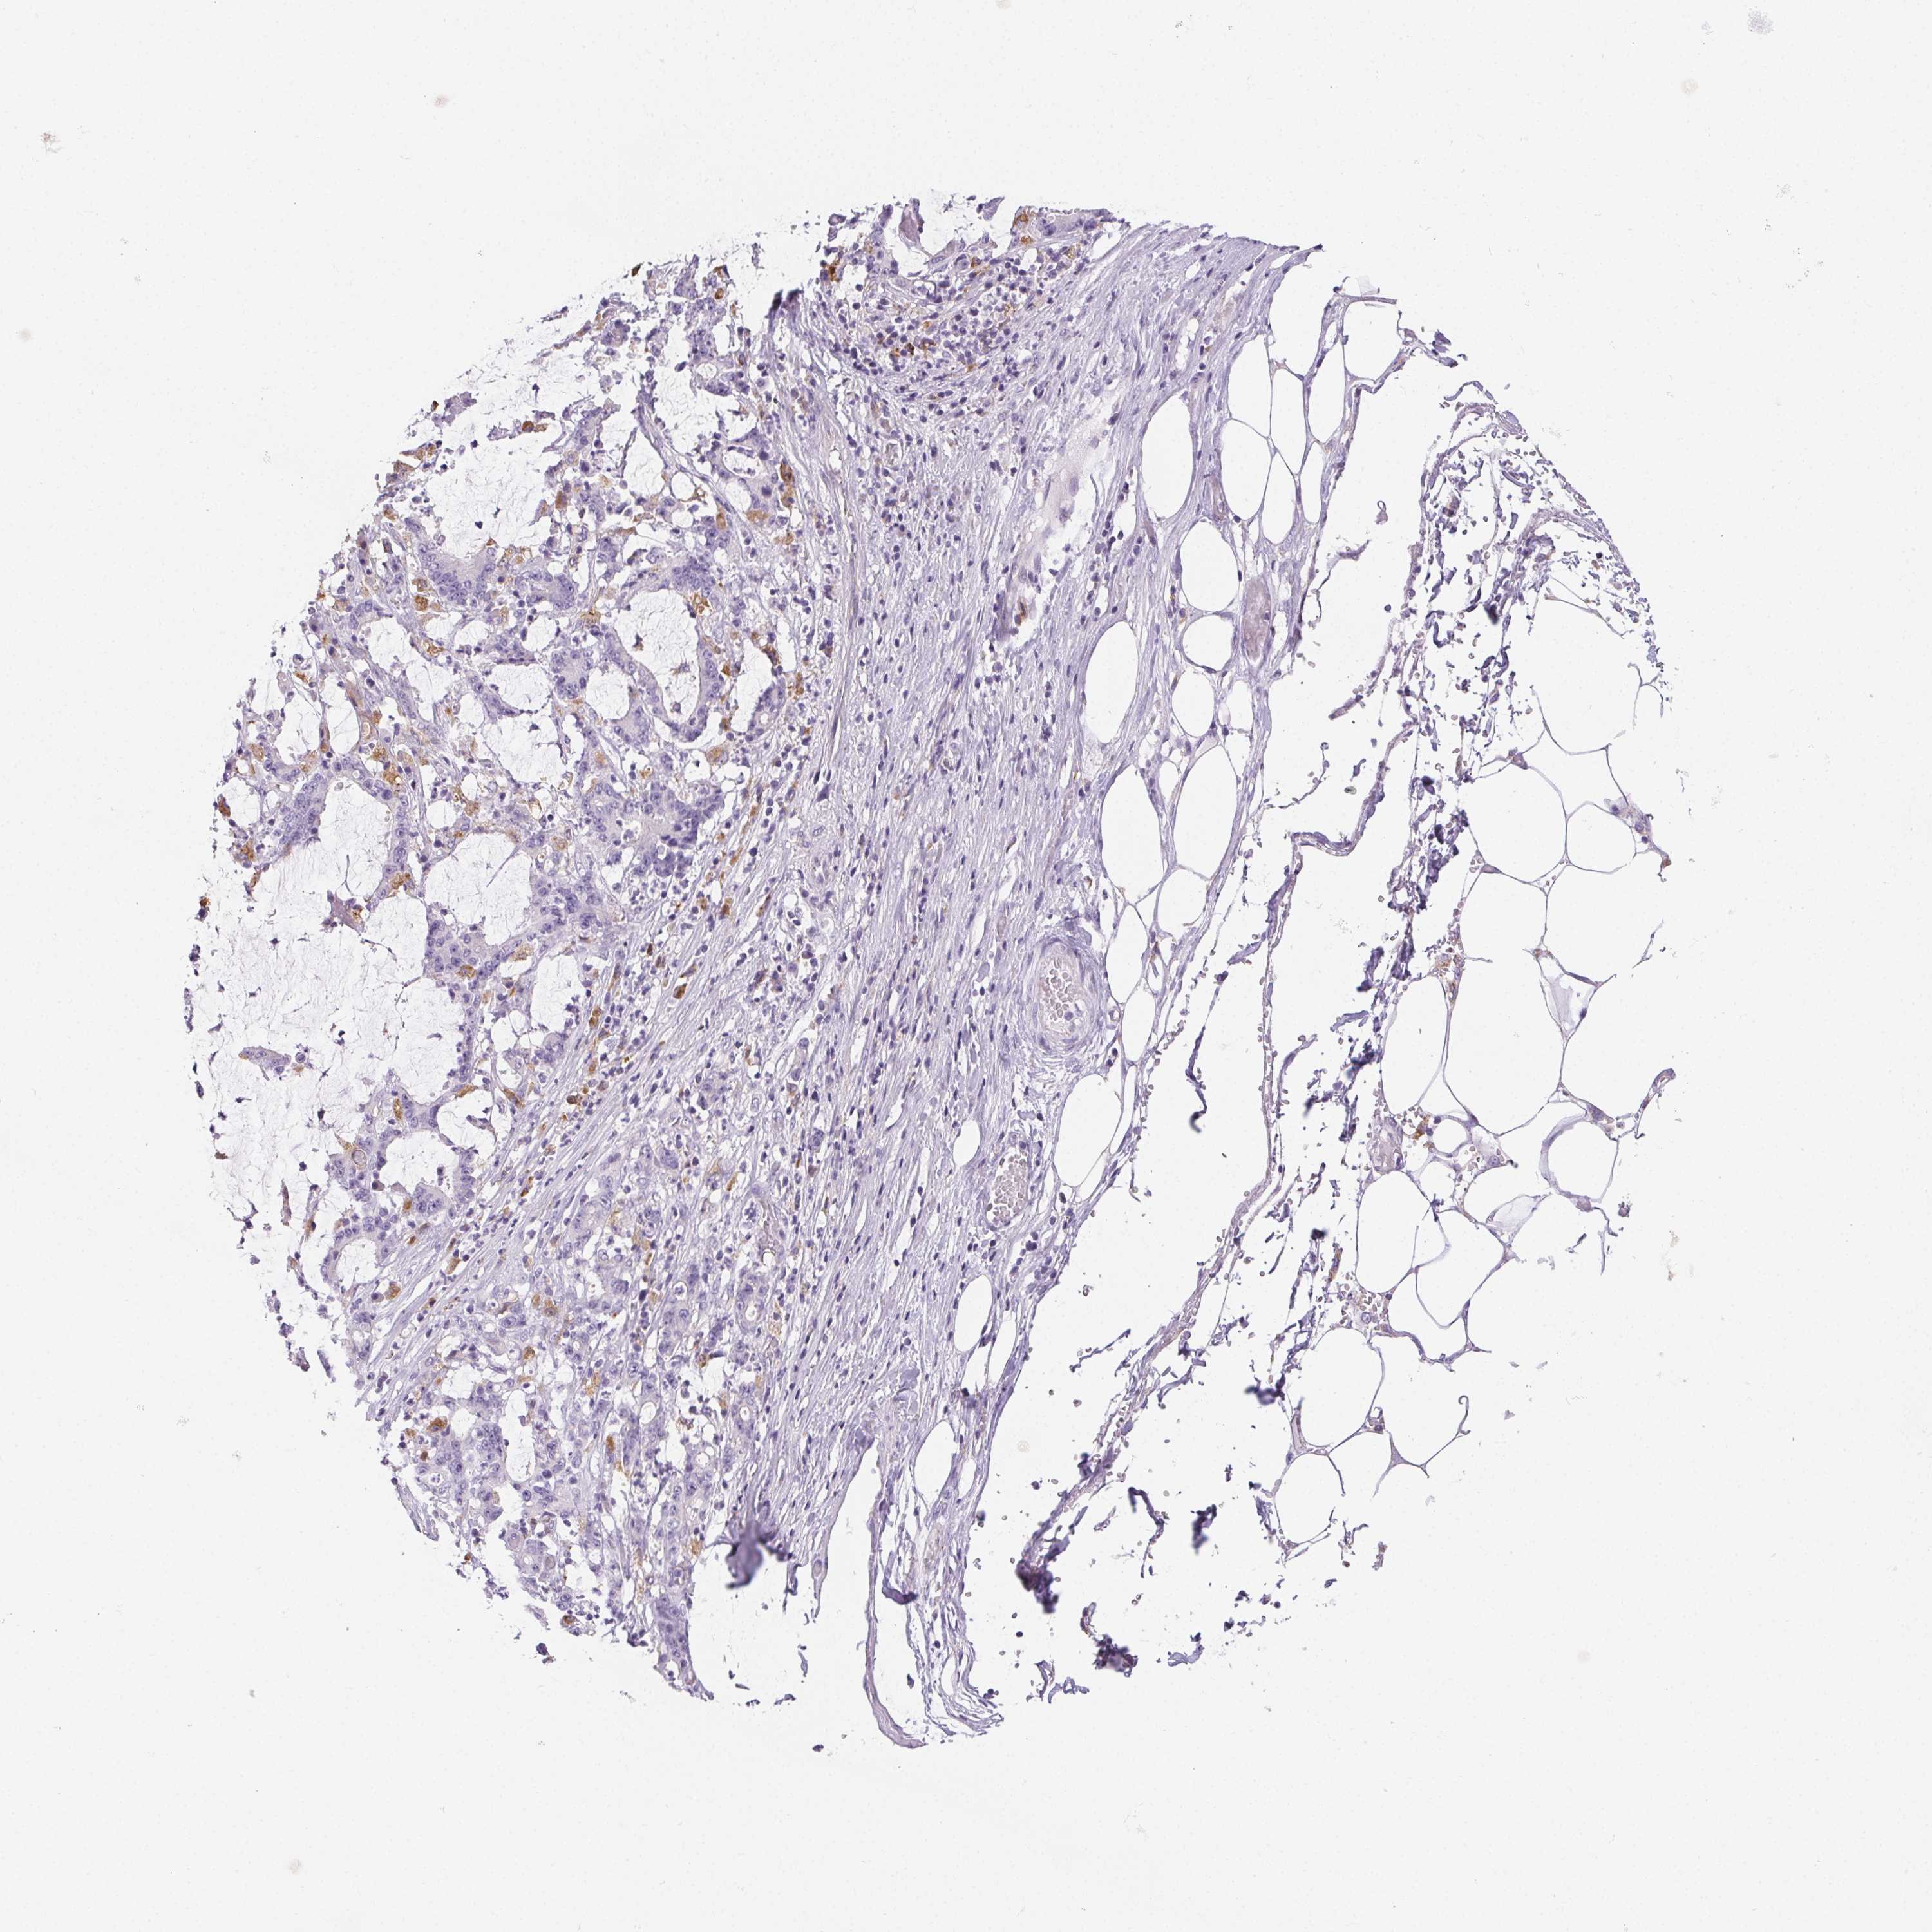

STOMACH CANCER - Protein expressioni

A mouse-over function shows sample information and annotation data. Click on an image to view it in a full screen mode. Samples can be filtered based on level of antibody staining by selecting one or several of the following categories: high, medium, low and not detected. The assay and annotation is described here.

Note that samples used for immunohistochemistry by the Human Protein Atlas do not correspond to samples in the TCGA dataset.

Antibody stainingi

Antibody staining in the annotated cell types in the current human tissue is reported as not detected, low, medium, or high, based on conventional immunohistochemistry profiling in selected tissues. This score is based on the combination of the staining intensity and fraction of stained cells.

Each image is clickable and will lead to virtual microscopy that enables deeper exploration of all samples and also displays staining intensity scores, fraction scores and subcellular localization as well as patient and tissue information for each sample.

Antibody HPA057052

Antibody CAB034892

Staining

High

Medium

Low

Not detected

Intensity

Strong

Moderate

Weak

Negative

Quantity

>75%

75%-25%

<25%

None

Location

Nuclear

Cytoplasmic/membranous

Cytoplasmic/membranous,nuclear

Adenocarcinoma, NOS